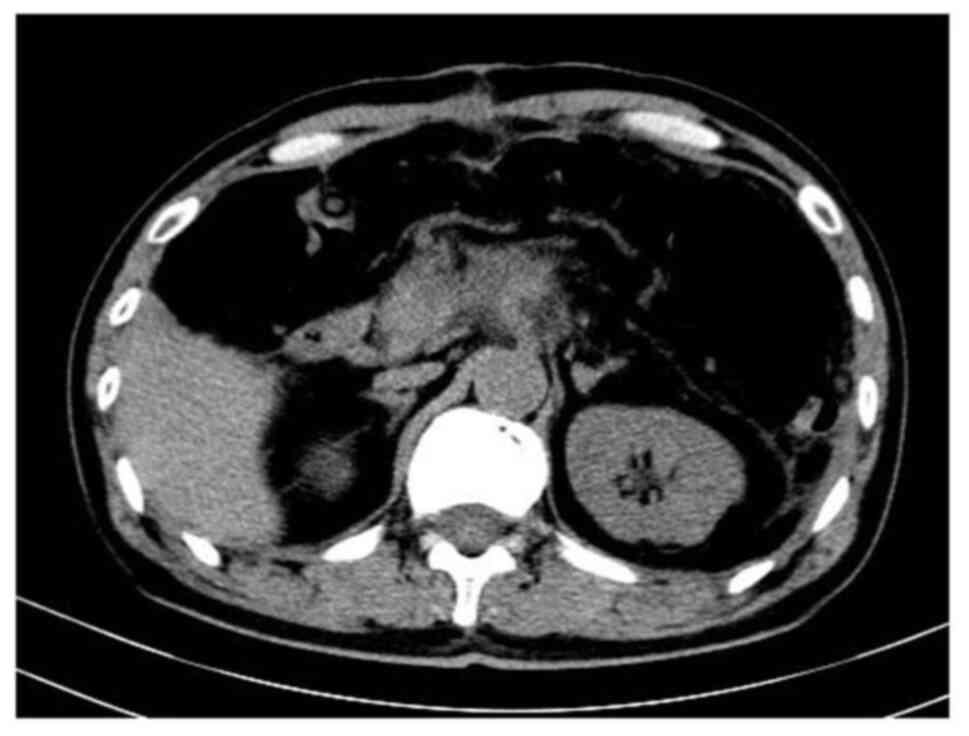

During the operation, multiple gastrointestinal surgery experts were consulted. In agreement with the consensus recommendation, the small intestine and the sigmoid colon were cut 5 cm away from the mass and closed, and 15 cm of the small intestine and 10 cm of the long intestine were removed. The long sigmoid colon was removed and the mass was resected after removing part of the bladder wall. Continuous suture was performed to repair the bladder. The small intestine and sigmoid colon were sutured end to end and the mesentery was repaired. The colon anastomosis was ~35 cm from the anus and the small intestine anastomosis was 85 cm away from the ileocecal loop. After the operation, meticulous hemostasis and abdominal cavity irrigation were performed, a drainage tube was inserted and the trocar laparoscopic hole was closed layer by layer. The operation lasted 97 min and the intraoperative bleeding volume was 72 ml. The operation was smooth, the anesthesia was satisfactory and the patient returned to the ward safely. After the operation, the patient was treated with antibiotics, stomach nourishment and fluid supplement. A plain abdominal CT scan showed postoperative tumor occupation changes in the pancreas and peripancreatic inflammatory exudation 8 days post-surgery (Fig. 3).

Figure 3.

Plain abdominal CT scan showing the postoperative changes of the pancreas. CT, computerized tomography.